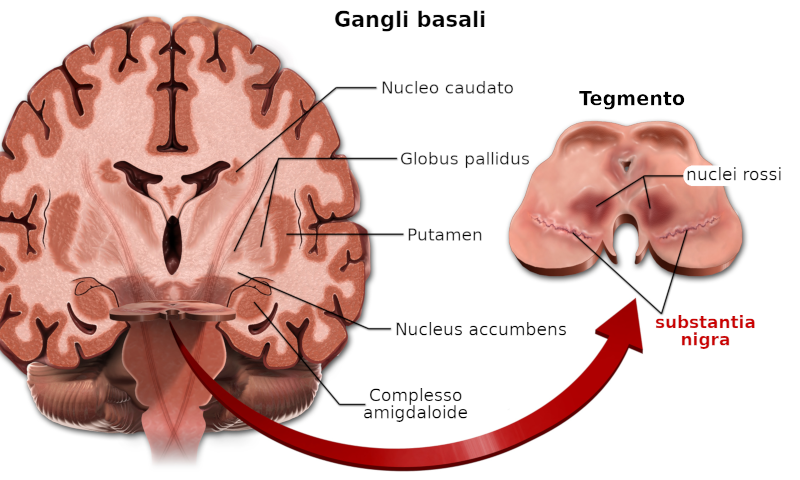

La substantia nigra, insieme ad altri quattro nuclei, fa parte dei gangli basali, che si trovano nel mesencefalo, posteriormente ai peduncoli cerebrali. Sono strutture pari, una a destra ed una a sinistra.

- la pars reticulata (SNpr): i neuroni della pars reticulata sono principalmente soggetti all'azione del neurotrasmettitore GABA, che ha una funzione di modulazione della risposta neuronale

- la pars compacta (SNpc): La funzione più importante della pars compacta è il controllo motorio, sebbene il ruolo della substantia nigra nel controllo motorio sia indiretto. La pars compacta invia un input eccitatorio al corpo striato, con conseguente rilascio di GABA. Ciò fa sì che le vie talamocorticali si eccitino e trasmettano i segnali dei motoneuroni alla corteccia cerebrale per consentire l'inizio del movimento. Il ruolo motorio della pars compacta può coinvolgere il controllo motorio fine. È fortemente coinvolta nelle risposte apprese agli stimoli. È importante anche per l'apprendimento spaziale, le osservazioni sul proprio ambiente e la posizione nello spazio.

La pars compacta svolge anche un ruolo nell'elaborazione temporale.

È situato tra i gangli basali della sottocorticale del cervello anteriore. È un componente cruciale per i sistemi motorio e di ricompensa; coordina aspetti cognitivi multipli, compresa la pianificazione motoria e dell'azione, la decisionalità, la motivazione e la precezione della ricompensa.

La substantia nigra gioca un ruolo importante nel funzionamento cerebrale, con riferimento particolare al movimento degli occhi, alla pianificazione motoria, alla ricerca del piacere e della ricompensa, all'apprendimento ed alla dipendenza. Molti degli effetti generati dalla substantia nigra sono mediati dal Corpo striato (→).